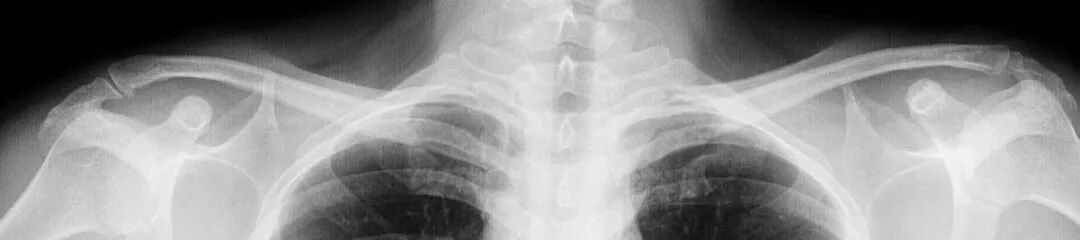

X 光

# X光检查 #

# 胸透和胸片/DR检查是什么 #

俗称拍片,最常见的影像检查,X射线具有穿透性,但人体组织间有密度和厚度的差异,当X射线透过人体不同组织时,被吸收的程度不同,经过显像处理后即可得到不同的影像。

胸透和胸片DR作用

胸透和胸片主要用于检查诊断肺部疾病、心脏的大小、肋骨、胸膜、胸壁纵隔、支气管。为减少X线的损害,患者做检查不宜过多。

胸片DR和胸透还是有很大的区别的,当然它们都是检查胸部,也就是看肺这一块的。但是它们的区别还是比较大的,首先第一点它的辐射剂量有很大的差别,胸片DR,它的辐射剂量是非常的小,而胸透相对来说就要大一些了,主要是跟它辐射的时间有关系。

做胸片DR检查的话,它辐射的时间是非常短的,一般也就是零点零几秒的时间,非常的短,而胸透检查它这个辐射时间相对来说就要长一些了,一般是需要十秒钟的时间。当然如果发现有可疑的病灶,可能需要看的时间要更长一些了。正因为是这样,所以现在很多医院已经基本上取消了胸透检查了,都是用胸片来进行替代。

胸片的话一般是可以照出一张片子来,而胸透只是医生通过目视,通过眼睛来看,看完之后得出一个纸质报告,是没有这种片子的。

胸部